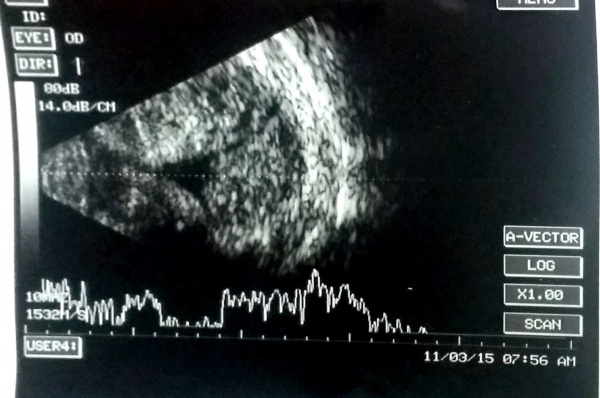

A case of choroidal hemangioma[6] with exudative RD. Note the limited after-movements.